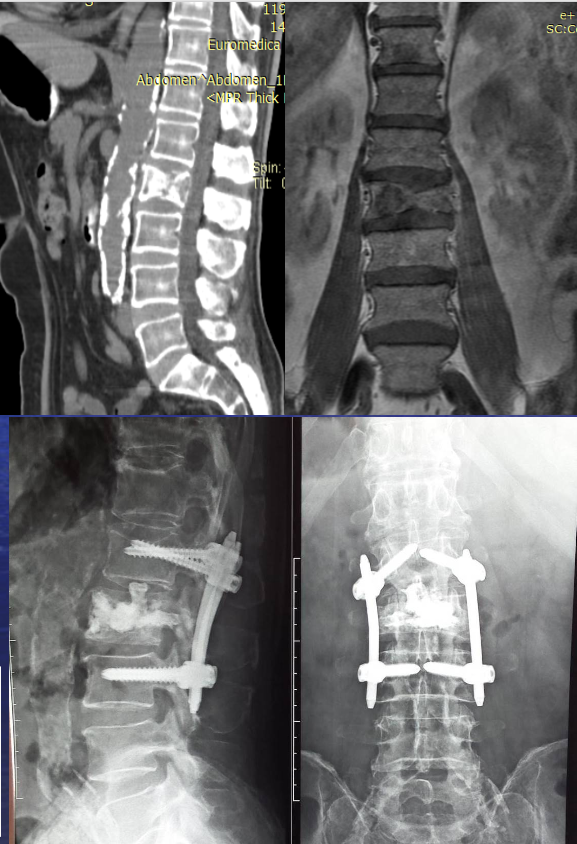

- Ενώ στον επόμενο ασθενή λόγω μεγάλης οστικής καταστροφής/ αστάθειας του Ο2 σπονδύλου έγινε και διαδερμική τοποθέτηση βιδών (ελάχιστα επεμβατική σπονδυλοδεσία): πάνω φαίνεται η αξονική και μαγνητική του ασθενούς και κάτω οι ακτινογραφίες. Αξίζει να σημειωθεί εδώ ότι λόγω της βαριάς κατάστασης του ασθενούς που δεν επέτρεπε την διενέργεια της επέμβασης με ολική αναισθησία ως συνήθως, αυτή έγινε με τοπική νάρκωση και επισκληρίδιο αναισθησία και δημοσιεύθηκε στο παρακάτω άρθρο: https://pmc.ncbi.nlm.nih.gov/articles/PMC8022040/